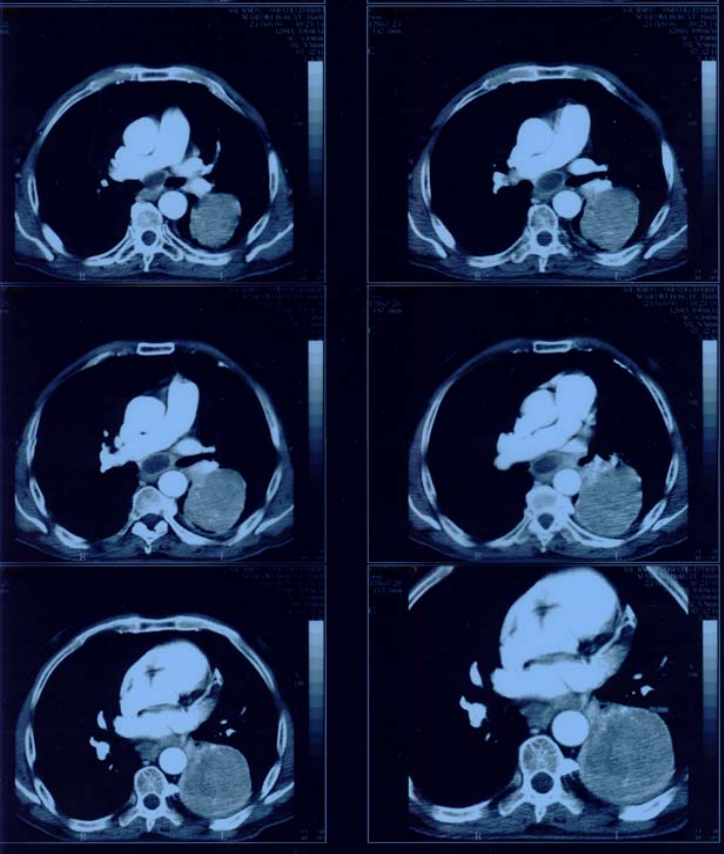

Observations on the report of a case of pulmonary adenocarcinoma with lymph node, hepatic and osseus metastasis.

Figure2